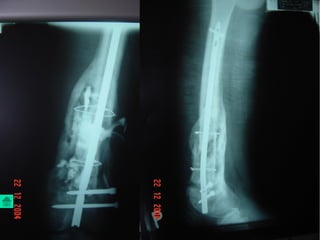

Baát ñoäng xöông

Coá ñònh ngoaøi:

 Coáñònhngoaøilaøphöôngphaùptieâuchuaåntrongvieâmxöông

khôùpgiaû.

- Theo ñuùng nguyeân taéc coá ñònh ngoaøi

- Giöõ trong moät thôøi gian daøi, coù theå moät naêm hoaëc hôn.

- Thayñinh neáu bònhieãm truøng chaânñinh

- Hai loaïi CÑN löïachoïn laø Ilizarov vaø khung ñôn giaûnduøng ñinh Chanz .

Ñinh, neïp:

 Nguy cô nhieãm truøng cao, nhöng moät soá

tröôøng hôïp cuõng duøng.